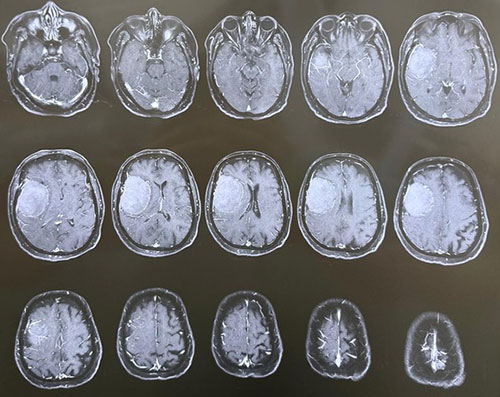

Surgical Highlights